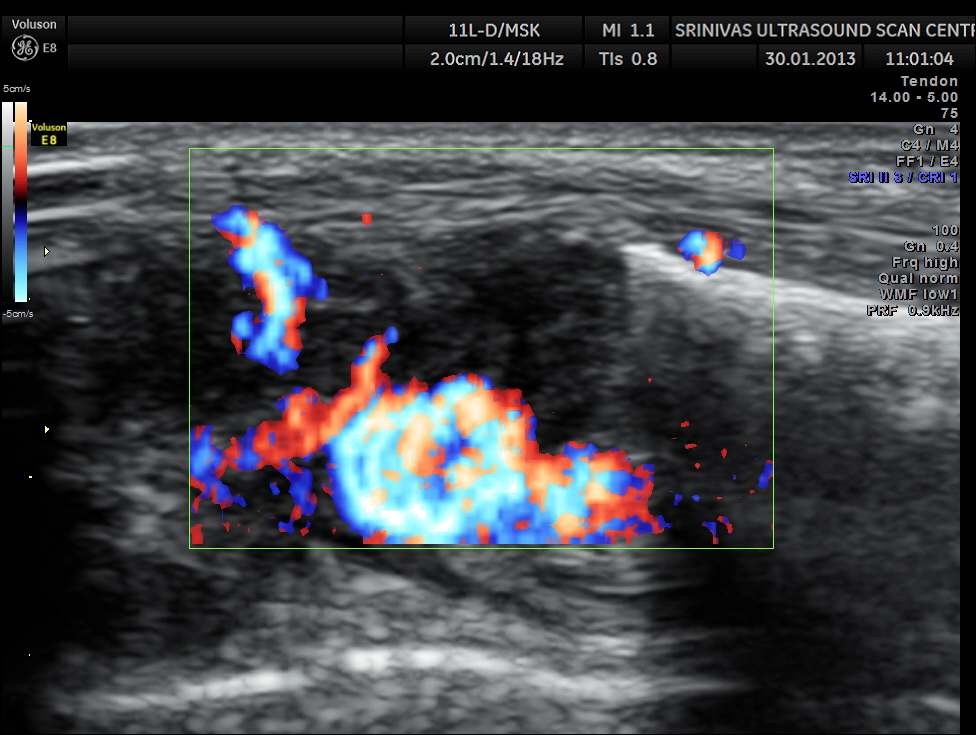

An indistinct hypo echoic mass was seen under a tendon and was well away from the surface of the bone .

Colour Doppler showed increased vascularity all around .

This case is presented to illustrate how musculo skeletal ultrasound and colour Doppler can be very useful to assess soft tissue pathology.